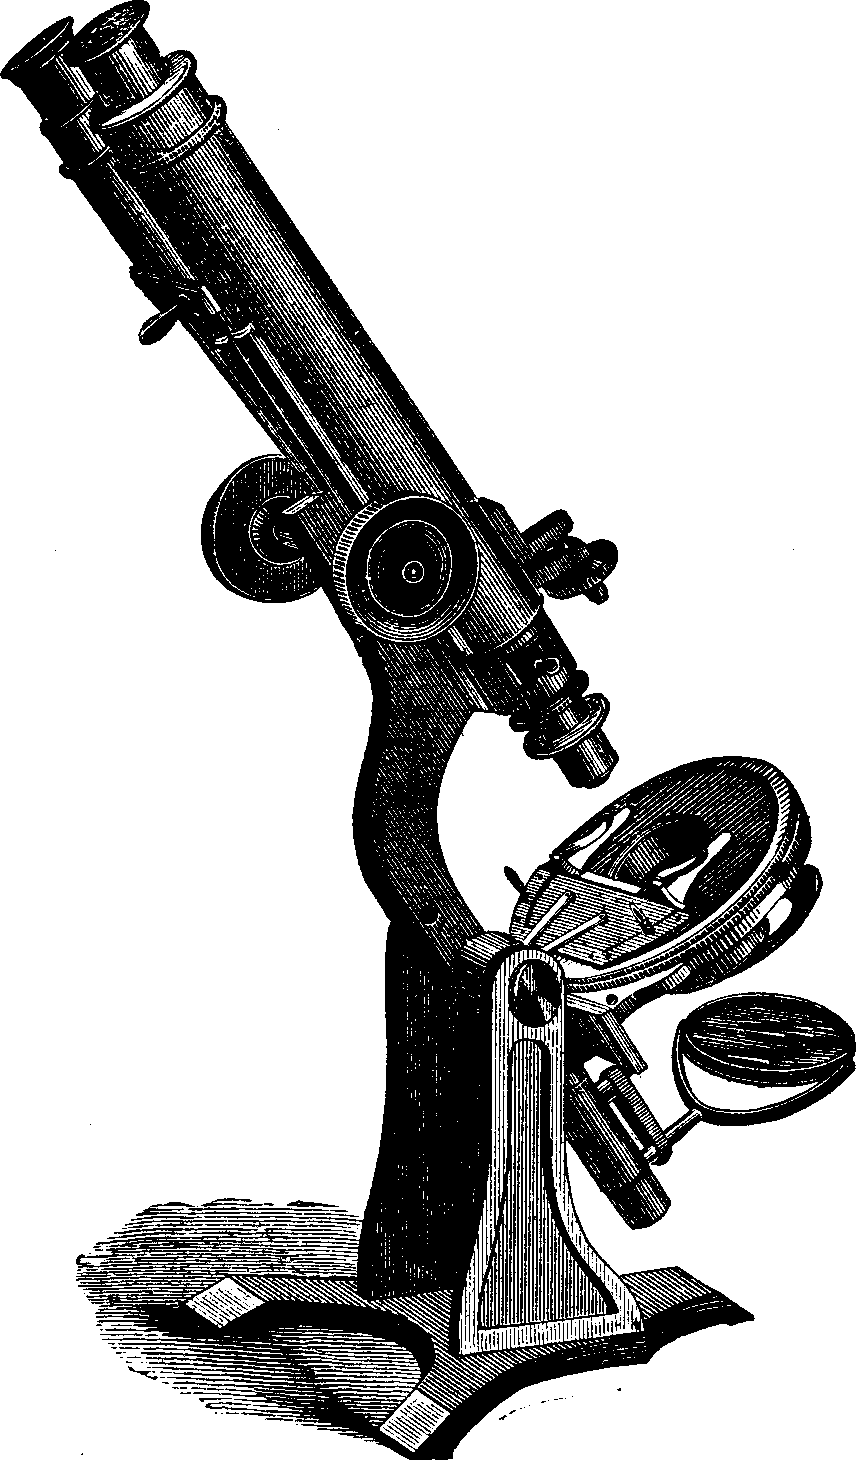

The physical act of generation is accomplished by the union of two cells; and as this conjugation is known to be so generally indispensable to the organization of life, we may fairly infer that it is a universal necessity. Investigations with the microscope have destroyed the hypothesis of "spontaneous generation." These show us that even the minutest living forms are derived from a parent organization.

Generation. So long as the vital principle remains in the sperm-cell, it lies dormant. That part of the cell which contains this principle is called the spermatozoön, which consists of a flattened body, having a long appendage tapering to the finest point. If it be remembered that a line is the one-twelfth part of an inch in length, some idea may be formed of the extreme minuteness of the body of a human spermatozoön, when we state that it is from 1/800 to 1/600 part of a line, and the filiform tail 1/50 of a line, in length. This life-atom, which can be discerned only with a powerful magnifying glass, is perfectly transparent, and moves about by executing a vibratile motion with its long appendage. Within this speck of matter are hidden the multifarious forces which, under certain favorable conditions, result in organization. Magnify this infinitesimal atom a thousand times, and no congeries of formative powers is perceived wherewith to work out the wonders of its existence. Yet it contains the principle, which is the contribution on the part of the male toward the generation of a new being.

The vital principle, represented in the sperm-cell by a spermatozoön, must be imparted to a germ-cell in order to effect impregnation. After touching each other, separate them immediately, and observe the result. If, with the aid of a powerful lens, we directly examine the spermatozoön, it will be perceived that, for a short time, it preserves its dimensions and retains all its material aspects. But it does not long withstand the siege of decay, and, having fulfilled its destiny, loses its organic characteristics, and begins to shrink.

The microscope reveals the fact that matter measuring only 1/120000 of an inch diameter may be endowed with vitality, and that countless numbers of animalcules often inhabit a single drop of stagnant water. These monads do not vary in form, whether in motion or at rest. The life of one, even, is an inexplicable mystery to the philosopher. Ehrenberg writes: "Not only in the polar regions is there an uninterrupted development of active microscopic life, where larger animals cannot exist, but we find that those minute beings collected in the Antarctic expedition of Captain James Ross exhibit a remarkable abundance of unknown, and often most beautiful forms."